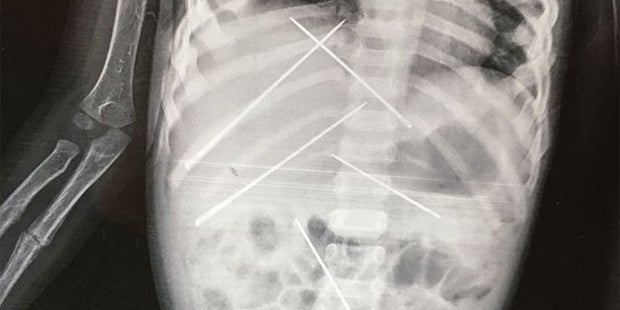

Sieben Nadeln wurde in den Körper des Kleinkindes gestochen.

Die 3-Jährige wurde mit starkem Fieber ins SKMM-Krankenhaus gebracht. Auf einem Röntgenbild entdeckten die Ärzte schließlich, dass gleich sieben, jeweils rund fünf Zentimeter lange Nadeln, in das Kleinkind gestochen wurden. Diese Nadeln konnten die Mediziner nicht herausnehmen, ohne den Körper weiter zu schädigen. Erst nach drei Tagen entschieden sich die Ärzte dann dennoch zur Operation. Die Verletzungen und inneren Entzündungen waren aber zu schwer – das Mädchen starb drei Tage später.

Die Polizei hat nun Ermittlungen aufgenommen. Die Röntgenbilder legten die Vermutung nahe, dass das Kind missbraucht wurde. Verdächtigt wird ein Mann, für den die Mutter des Kindes als Haushaltshilfe arbeitet. Er soll schwarze Magie praktiziert und das Mädchen als menschliche Voodoo-Puppe gequält haben. Zudem wurde die 3-Jährige auch sexuell missbraucht.